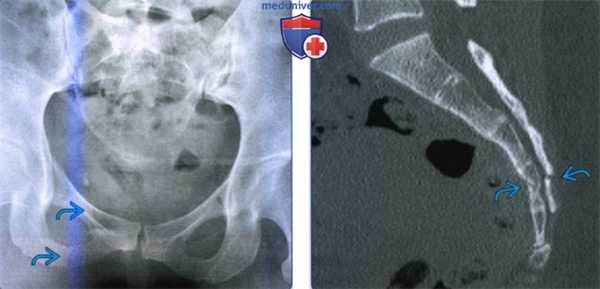

• Поперечный перелом крестца или копчика:

о Лучше всего визуализируется на рентгенограмме в боковой проекции или на сагиттальном срезе при КТ

о Чаще определяется угловая деформация, а не отдельная линия перелома

• Переломы промежности:

о Переломы верхней и нижней ветвей лобковой кости, заднее кольцо не повреждено

• Изолированные переломы ветви лобковой кости:

о При изолированной травме обычно отсутствует смещение

(Слева) На рентгенограмме в передне-задней проекции определяются переломы верхней и нижней ветвей лобковой кости, возникшие вследствие падения пациента в положении сидя.

(Справа) КТ крестца, сагиттальный срез: у этого же пациента определяется поперечный перелом крестца на уровне.